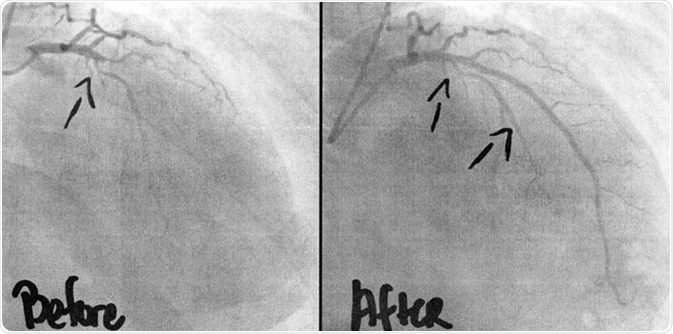

Coronary Angiogram imaging, before, and after 3 stents, and ballooning of two occlusions was performed intravenously by a cardiac surgeon. A life saving intervention for the 54 year old man. Image Credit: KellyNelson/ Shutterstock